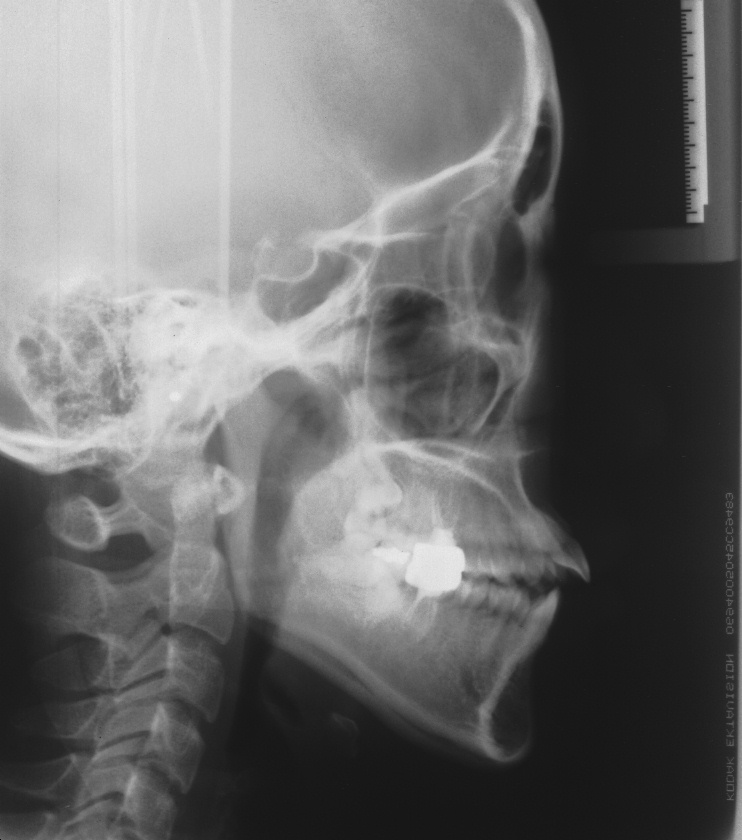

치료 후 사진입니다.